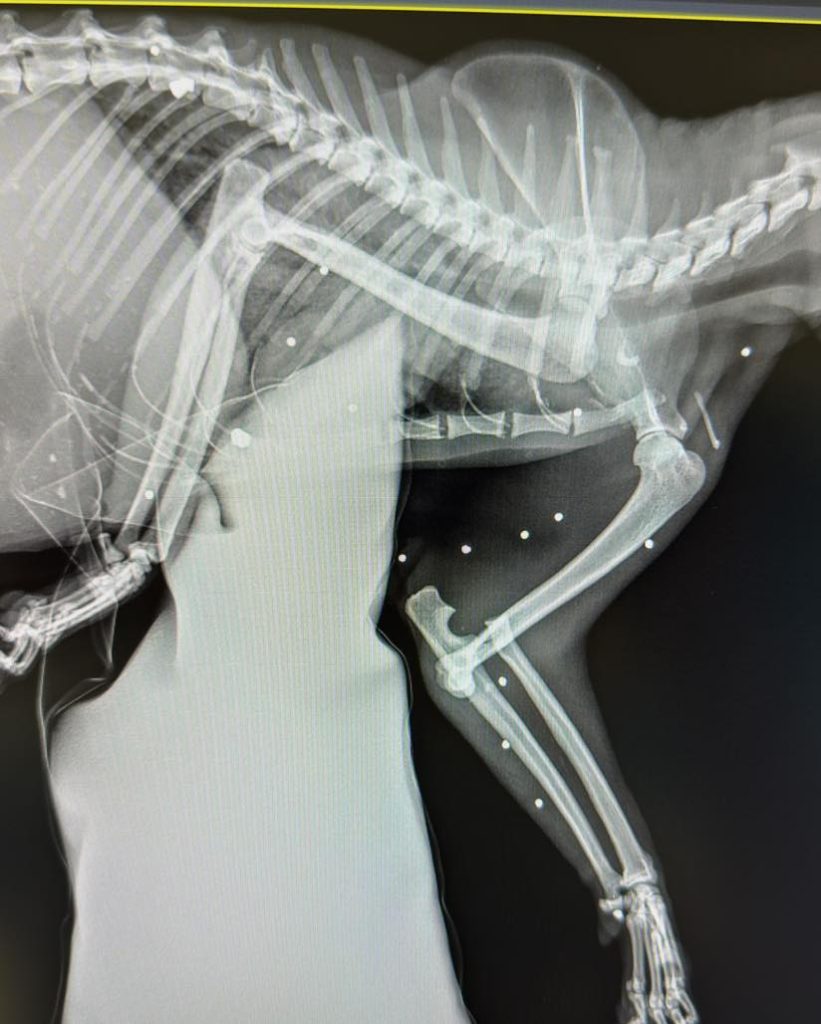

Pod opiekę Nyskiego Pogotowia Opiekuńczo – Adopcyjnego dla Zwierząt Łapa trafił w środę ranny kotek. Zwierzę trafiło pod opiekę specjalistów z podejrzenim zwichnięcia stawu łokciowego miało uraz przedniej kończyny. Po wykoanniu zdjęć RTG okazało się, że to nie jedyny uraz zwierzęcia. W głowie, jamie brzusznej o klatce piersiowej odkryto ponad 30 śrucin.

– Dziś pod naszą opiekę trafił kot, u którego doszło do zwichnięcia stawu łokciowego z towarzyszącym przemieszczeniem kości łokciowej, najprawdopodobniej na skutek ludzkiego okrucieństwa! Zdjęcia RTG wykazały nie tylko uraz przedniej łapy, ale również obecność w ciele kota ponad 30 kulek śrutu! Kim trzeba być? Żeby zrobić sobie ze zwierzęcia żywą tarczę!? Na usta cisną się same najgorsze słowa! – piszą na swojej profilu na facebooku Animalsi z Nyskiej ŁAPY.

Badania diagnostyczne wykazały u kota silny stan zapalny, w trybie pilnym trafił na stół operacyjny w celu ratowania przedniej łapy. Następnie zwierze czekają kolejne zabiegi mające na celu usunięcie śrutu z ciała.